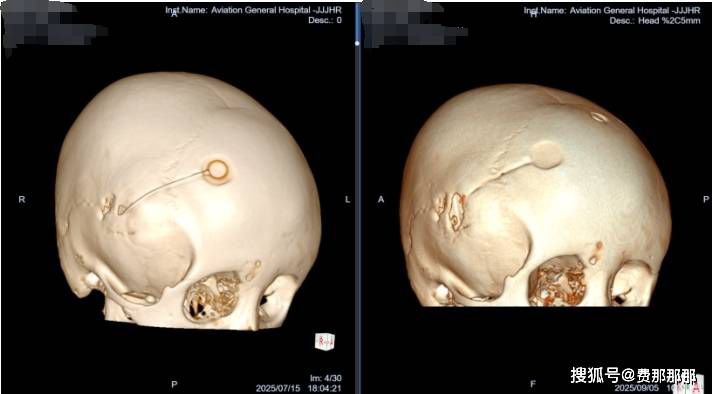

2025年7月,13岁的小廖因“进行性加重性行走障碍,左侧足外翻,右侧肢体活动不利、抖动”找到北京航空总医院肖庆主任。这本应享受校园生活的年纪,她却已经在病痛折磨中度过了十年之久:3岁时发现右颞蛛网膜囊肿,当地医院行开颅囊肿剥离手术;4岁时囊肿复发增大,又行囊肿-腹腔分流术;9岁时出现分流管感染,不得不行分流管拔除术并植入囊肿储液囊(Ommaya囊)……随后多年,虽然经历了多次手术和抗感染治疗,小廖的病情仍然逐渐加重——脑室系统扩张、右颞囊肿张力不断增加、中线结构移位明显。这不仅影响了她的运动功能(行走障碍、肢体活动不利),也影响了她的生活技能和认知发展。

一期清创:利用软性内镜的灵活性和广视野,一期手术同时完成感染装置取出、脑室系统探查与灌洗。术中,肖庆主任凭借精湛的技术和丰富的经验,通过神经内镜精准探查囊肿腔,发现原囊肿造瘘与脑室颞角贯通,颞角脉络丛稍苍白。随后,团队成功拔除原分流管,将腹腔端分流管连接至脑室引流管,确保引流通畅。术后,脑脊液NGS检查发现腐生葡萄球菌、表皮葡萄球菌感染,这也印证了肖庆主任在门诊的第一判断,团队立即给予万古霉素抗炎治疗,监测脑脊液逐步改善,直至各项指标均达到合格。

二期重建:待感染控制后,及时实施ETV等脑脊液循环通路重建手术,这是避免再次置管、获得长期良好疗效的保障。术中,肖庆主任通过内镜进入脑室,发现脑室壁内欠光滑,透明隔破溃,室间孔向左侧扭曲变形。在三脑室底,团队以双腔球囊穿刺扩张瘘口直径至6mm,松解基底池粘连,并冲洗脑室。